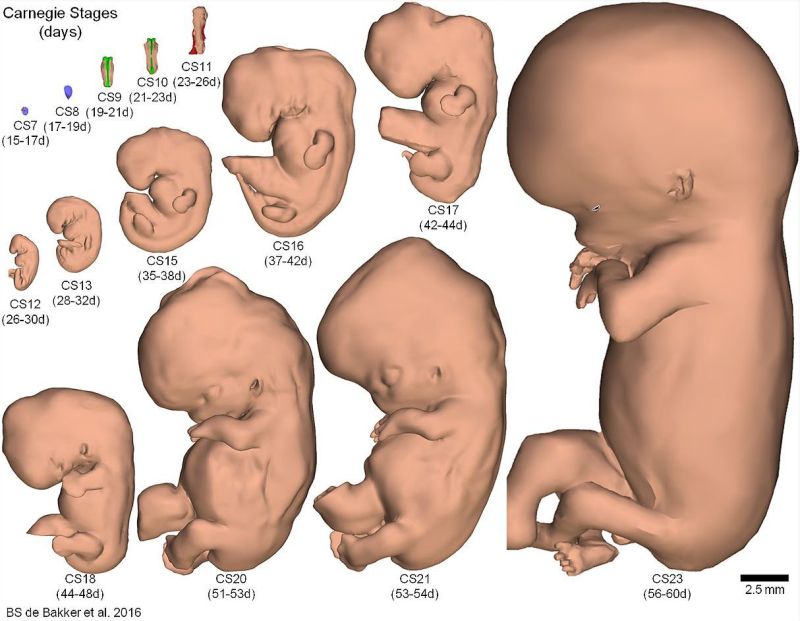

Ученые Академического медицинского центра в Амстердаме идентифицировали и промаркировала 150 структур и органов тела эмбрионов, после чего реконструировали их трехмерные компьютерные модели.

Результаты исследований сгруппировали в единый атлас развития эмбриона в период от 15-17 до 56-60 дня после зачатия.

Все модели были классифицированы по стадиям развития и превращены в интерактивный формат 3D-PDF, который находится в свободном доступе.

Атлас позволяет рассмотреть как эмбрион в целом, так и его отдельные структуры, органы и системы.

Для более полного понимания ученые указали размеры эмбриона в миллиметрах и по сравнению с ладонью взрослого человека.